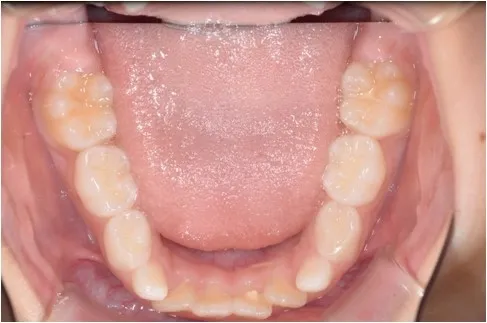

【治療前 下顎】

【治療開始から1年後 下顎】